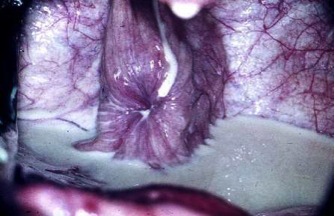

Fossa Glandis

Sinus urethralis

urethra

preputium